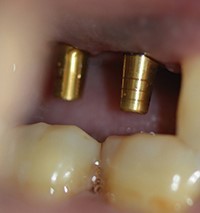

استخوان های خودبخود تولید شده که از استئوتومی پیشین تشکیل شده اند، با مقدار کمی از مواد پیوندی کورتیکو اسفنجی (Raptos (Citagixix)) مخلوط شده و با یک قاشق جراحی کوچک پدالی به استئوتومی معرفی می شوند(Zoll-Dental) (شکل 9). دو ماکرو ایمپلنت 6.0 در 6.0 میلیمتر در محل های آماده شده با استفاده از گیرنده های Ultim متصل می شوند (شکل 10). به محض قرارگیری، حامل ها برداشته شدند و ایمپلنت با یک آچار پیچی در جای خود ثابت شد. به محض رسیدن به کف نازک سینوس و به طور مکانیکی فشار به آن، یک تخلیه کنترل شده منجر به ایمپلنت در ناحیه شماره 2 شد (شکل 11).

شکل 9. استخوان های خود به خود تولید شده با استئوتومی ها برداشت می شوند.

شکل 10. یک ماکرو ایمپلنت 6.0 در 6.0 میلیمتری (OCO Biomedical).